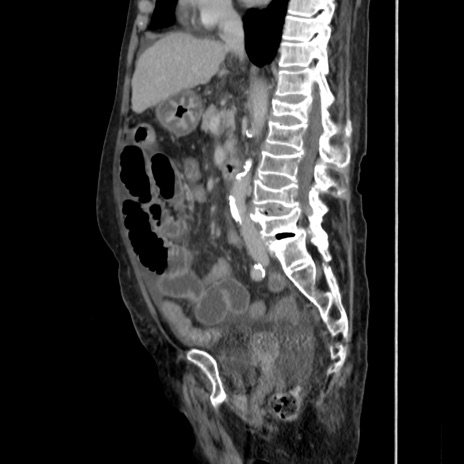

症例31(矢状断像)

【症例】80歳代 女性

【主訴】腹部膨満感

【現病歴】他院にて肝硬変にてフォロー中。1週間前から便秘、腹部膨満感、臍部腫瘤あり受診となる。

【既往歴】肝硬変

【身体所見】腹部膨隆あり、皮膚変化なし、疼痛なし。

【データ】WBC 4600、CRP 0.25